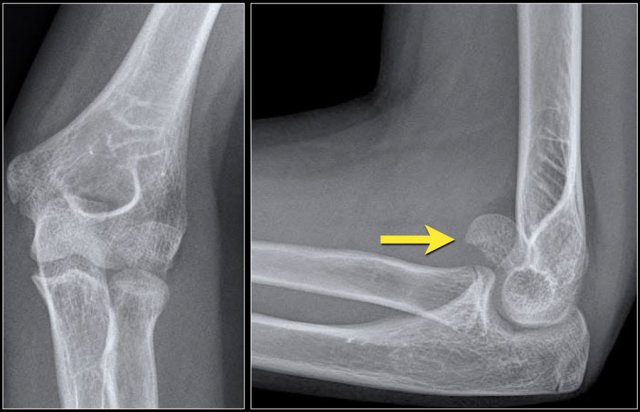

The rotation of the fracture fragment gives a typical appearance on the X-rays (arrow).

Capitellum fracture

While fractures of the lateral condyle occur in children between the age of 4 -10 years, isolated fractures of the capitellum are seen in children above the age of 12.

Capitellum fractures are uncommon.